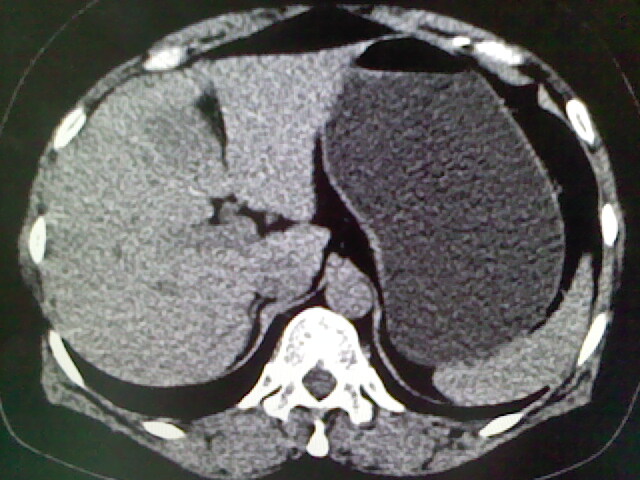

以下是引用卜一在2009-4-2 13:26:00的发言:[br]胆囊颈部结石伴胆囊炎!另:建议增强,待除外肝内占位及胆囊占位!

以下是引用liaoqiang在2009-4-2 16:23:00的发言:[br]胆囊是否切除?胆囊颈区致密影考虑金属夹?结石?肝脏右叶低密度影,考虑增强。